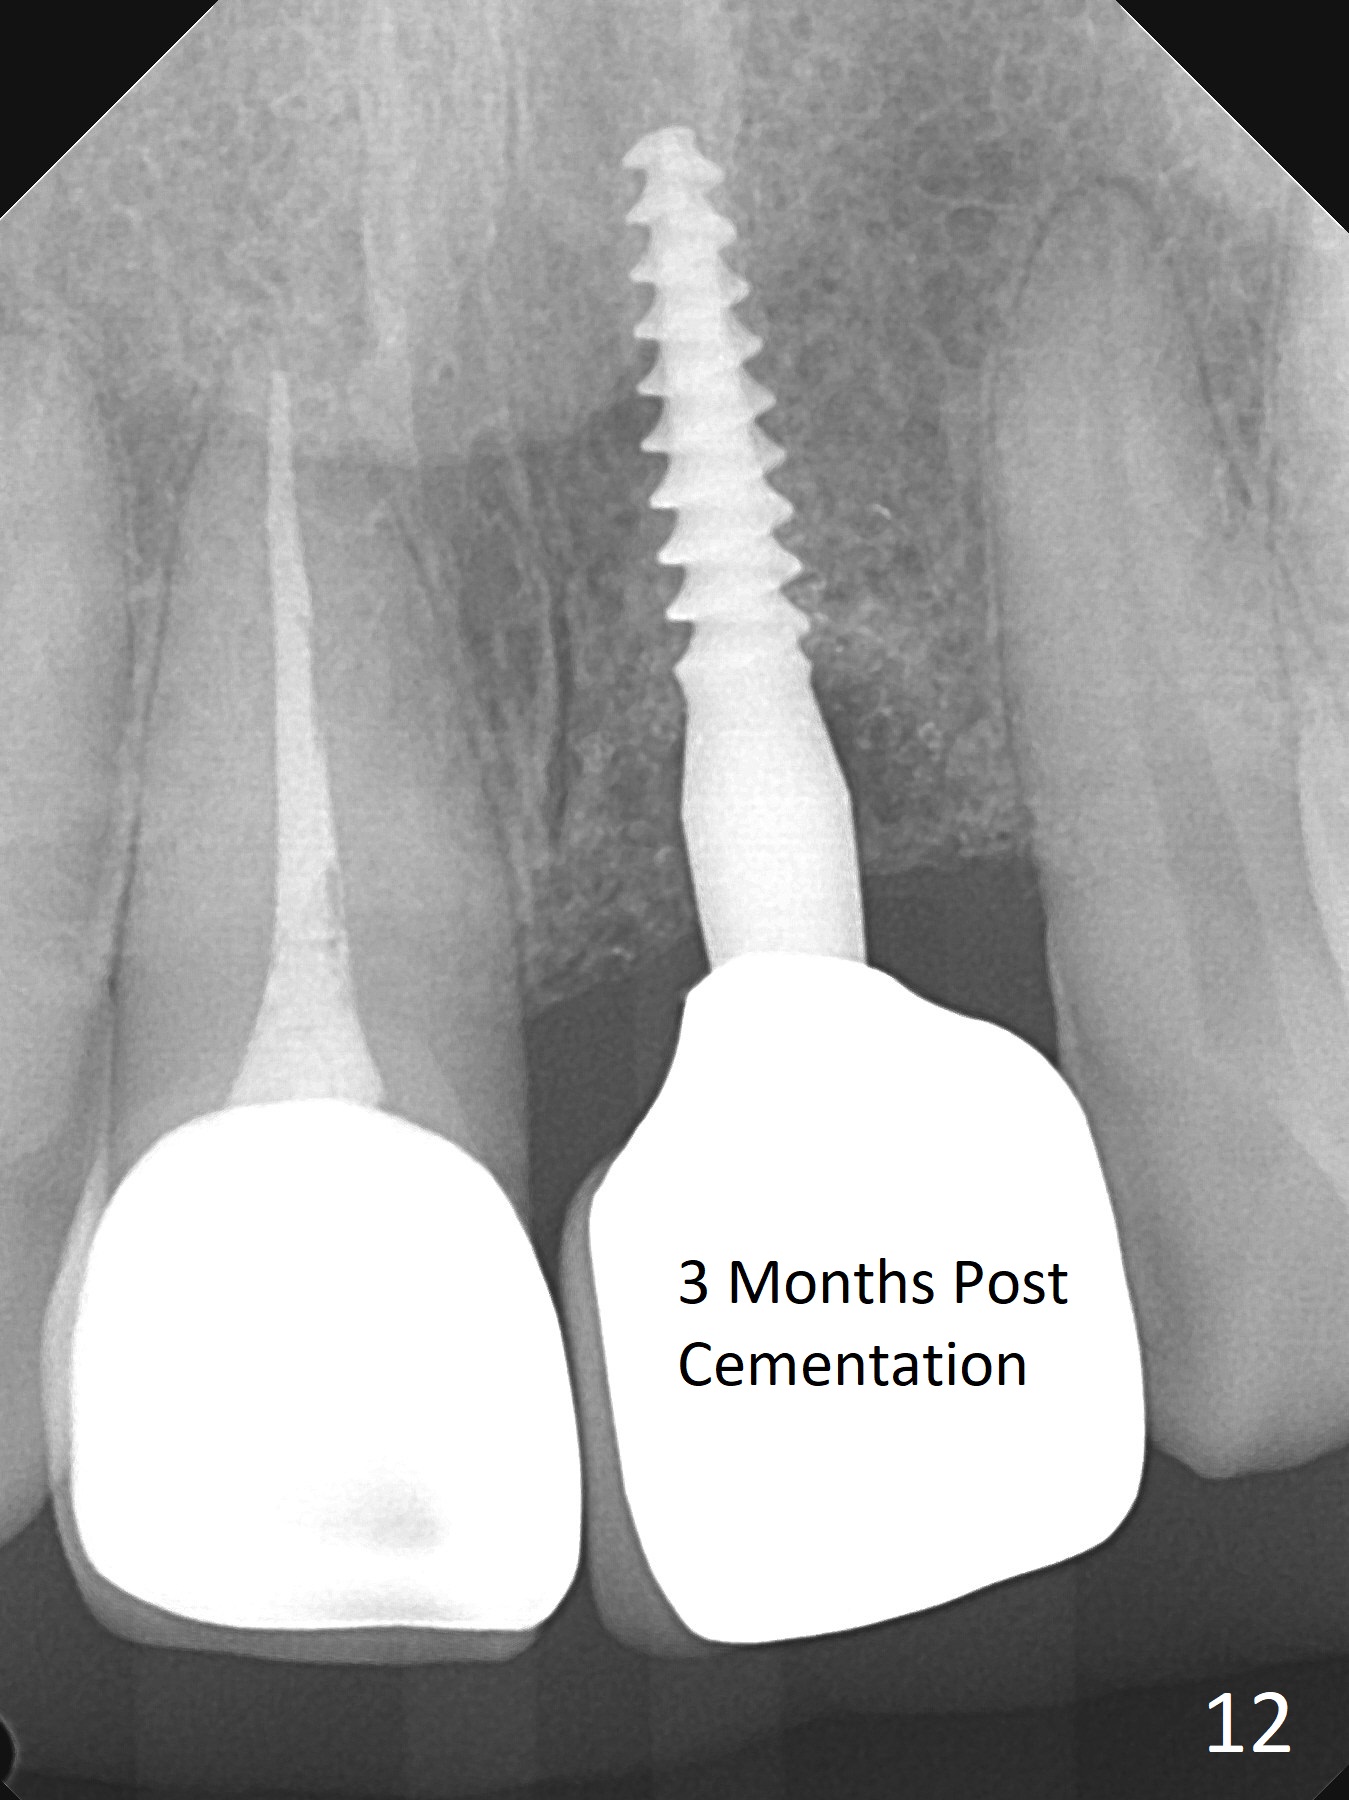

Except the depth, a 2.5x10 mm mini implant is placed with precision (in trajectory) at #9 (Fig.1-5). Confidence using surgical guide for the narrow ridge is enhanced due to placement of two digits against the buccal and palatal plates for tactile sensation. The depth issue is related to overprep with 2.2 mm drills. The torque is <15 Ncm. The immediate provisional is bonded to the neighboring teeth for retention. It appears that smaller drills should be made for guided surgery (such as 1.5 and 2.0 mm). The immediate provisional looks acceptable buccal and occlusal 3 weeks postop (Fig.6,7), although the palatal gingiva is erythematous (Fig.8, which is common after use of drill for access (tissue laceration), OHI offered). Three months postop (Fig.9), the palatal gingiva looks healthy (data not shown), while there is no bone loss around the implant (Fig.10). It remains the same 5 months postop (immediately post cementation, Fig.11) and 3,11 months post cementation (Fig.12,13). The labial gingiva is healthy (Fig.14), while the palatal one is less erythematous and edematous (Fig.15) than earlier (Fig.8).